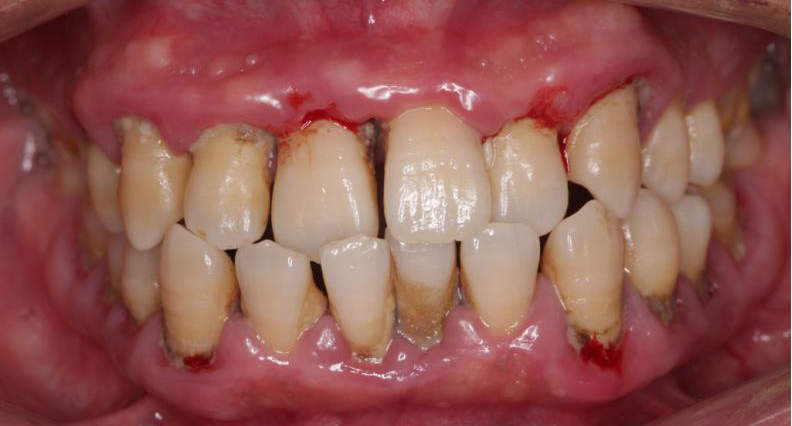

长沙60岁的赵大爷因为牙齿问题连日来无法吃东西,到湖南省人民医院马王堆院区口腔二科就诊,赵大爷告诉医生,自己因为牙齿原因苦不堪言,人也消瘦了不少。医生经过检查诊断赵大爷是患上了牙周炎,他的口腔内不仅有大量的牙结石堆积且牙龈红肿出血,还有严重的口臭,多颗牙齿摇摇欲坠,最终,只能拔除这些松动的牙齿,等待3个月后进行镶牙治疗。

很多人觉得奇怪,为什么没觉得痛,就会出现牙龈萎缩、红肿出血,甚至牙齿松动、脱落,张特主任指出,这就要认识什么是牙周炎。每个人口腔中都有牙菌斑,其粘附在牙齿表面或口腔其他软组织上。早期可以通过高效的刷牙去除,如果刷牙不彻底,牙菌斑会大量堆积形成硬化的牙结石,一旦牙结石达到相当程度,将不可避免刺激牙龈发炎,刷牙出血,就是单纯的依靠刷牙或口服消炎药已经无法去除病因。当炎症持续进展,将出现牙周袋、牙槽骨吸收、牙齿松动和口臭,发展为牙周炎。

张特介绍,之所以很多患者一开始没有感觉,是因为牙周炎是一个进展相对缓慢的疾病,早期的症状一般为牙龈红肿、偶尔刷牙及咬物出血、牙龈边缘出现刷牙不能去除的黄色牙结石、牙缝增宽、牙龈萎缩、牙齿酸痛敏感等,这些小毛病无关痛痒,所以容易被忽视。当牙周炎继续进展到严重期,患者的牙齿陆续出现松动,渐渐地咬物无力到最后无法进食,这时候已经为时已晚,有时甚至无力回天,只能拔除,接受镶牙或者种植牙,给患者带来经济负担,影响正常生活。